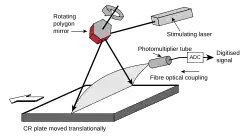

A lower-frequency light source that is insufficient in energy to create more Eu3+ ions can return the trapped electrons to the conduction band. As these mobilized electrons encounter Eu3+ ions, they release a blue-violet 400 nm luminescence.[4] This light is produced in proportion to the number of trapped electrons, and thus in proportion to the original X-ray signal. It can be collected often by a photomultiplier tube, which is clocked at a specific resolution or pixel capture frequency. The light is thereby converted to an electronic signal and significantly amplified. The electronic signal is then quantized via an ADC to discrete (digital) values for each pixel and placed into the image processor pixel map.

In phosphor plate radiography, the imaging plate is housed in a special cassette and placed under the body part or object to be examined and the x-ray exposure is made. The imaging plate is then run through a special laser scanner, or CR reader, that reads and converts the image to a digital radiograph. The digital image can then be viewed and enhanced using software that has functions very similar to other conventional digital image-processing software, such as contrast, brightness, filtration and zoom. CR imaging plates (IPs) can be retrofitted to existing exam rooms and used in multiple x-ray sites since IPs are processed through a CR reader (scanner) that can be shared between multiple exam rooms.[6]